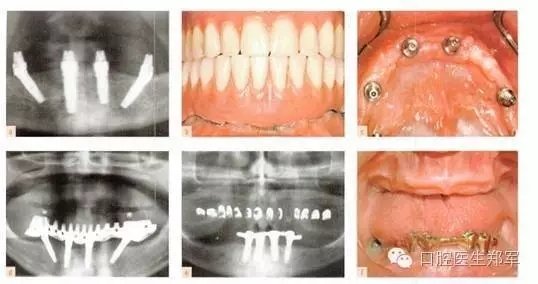

剩余牙槽骨的客觀解剖因素決定是否可以放置全牙弓種植體。在上頜骨,上頜竇提升通常是一個選擇,但是可能會導致極高的牙冠長度和不協(xié)調(diào)的冠根比。所謂“All on Four”,四個種植體支持式固定修復一直存在爭議,支持者和懷疑者都在等待長期的研究結果(圖3和4)。下頜后牙種植體的位置是由剩余牙槽嵴寬度和高度,以及不可預知的垂直方向上骨增量共同限制。5年的研究結果表明,種植體的存活和成功不受修復類型的影響。

圖3下頜的治療選擇。a到d 固定“All on Four”修復和遠中傾斜植入。(圖片由Dr. B Marshak提供)。e 和f 由四個種植體支撐的下頜覆蓋義齒。 |

圖4 種植支持的覆蓋義齒或4個傾斜種植體支持的固定種植體支持式的修復。“All on Four”已經(jīng)廣泛的傳播,懷疑者等待更可靠的證據(jù)結果。臨床圖像由Dr. B Marshak提供。 |